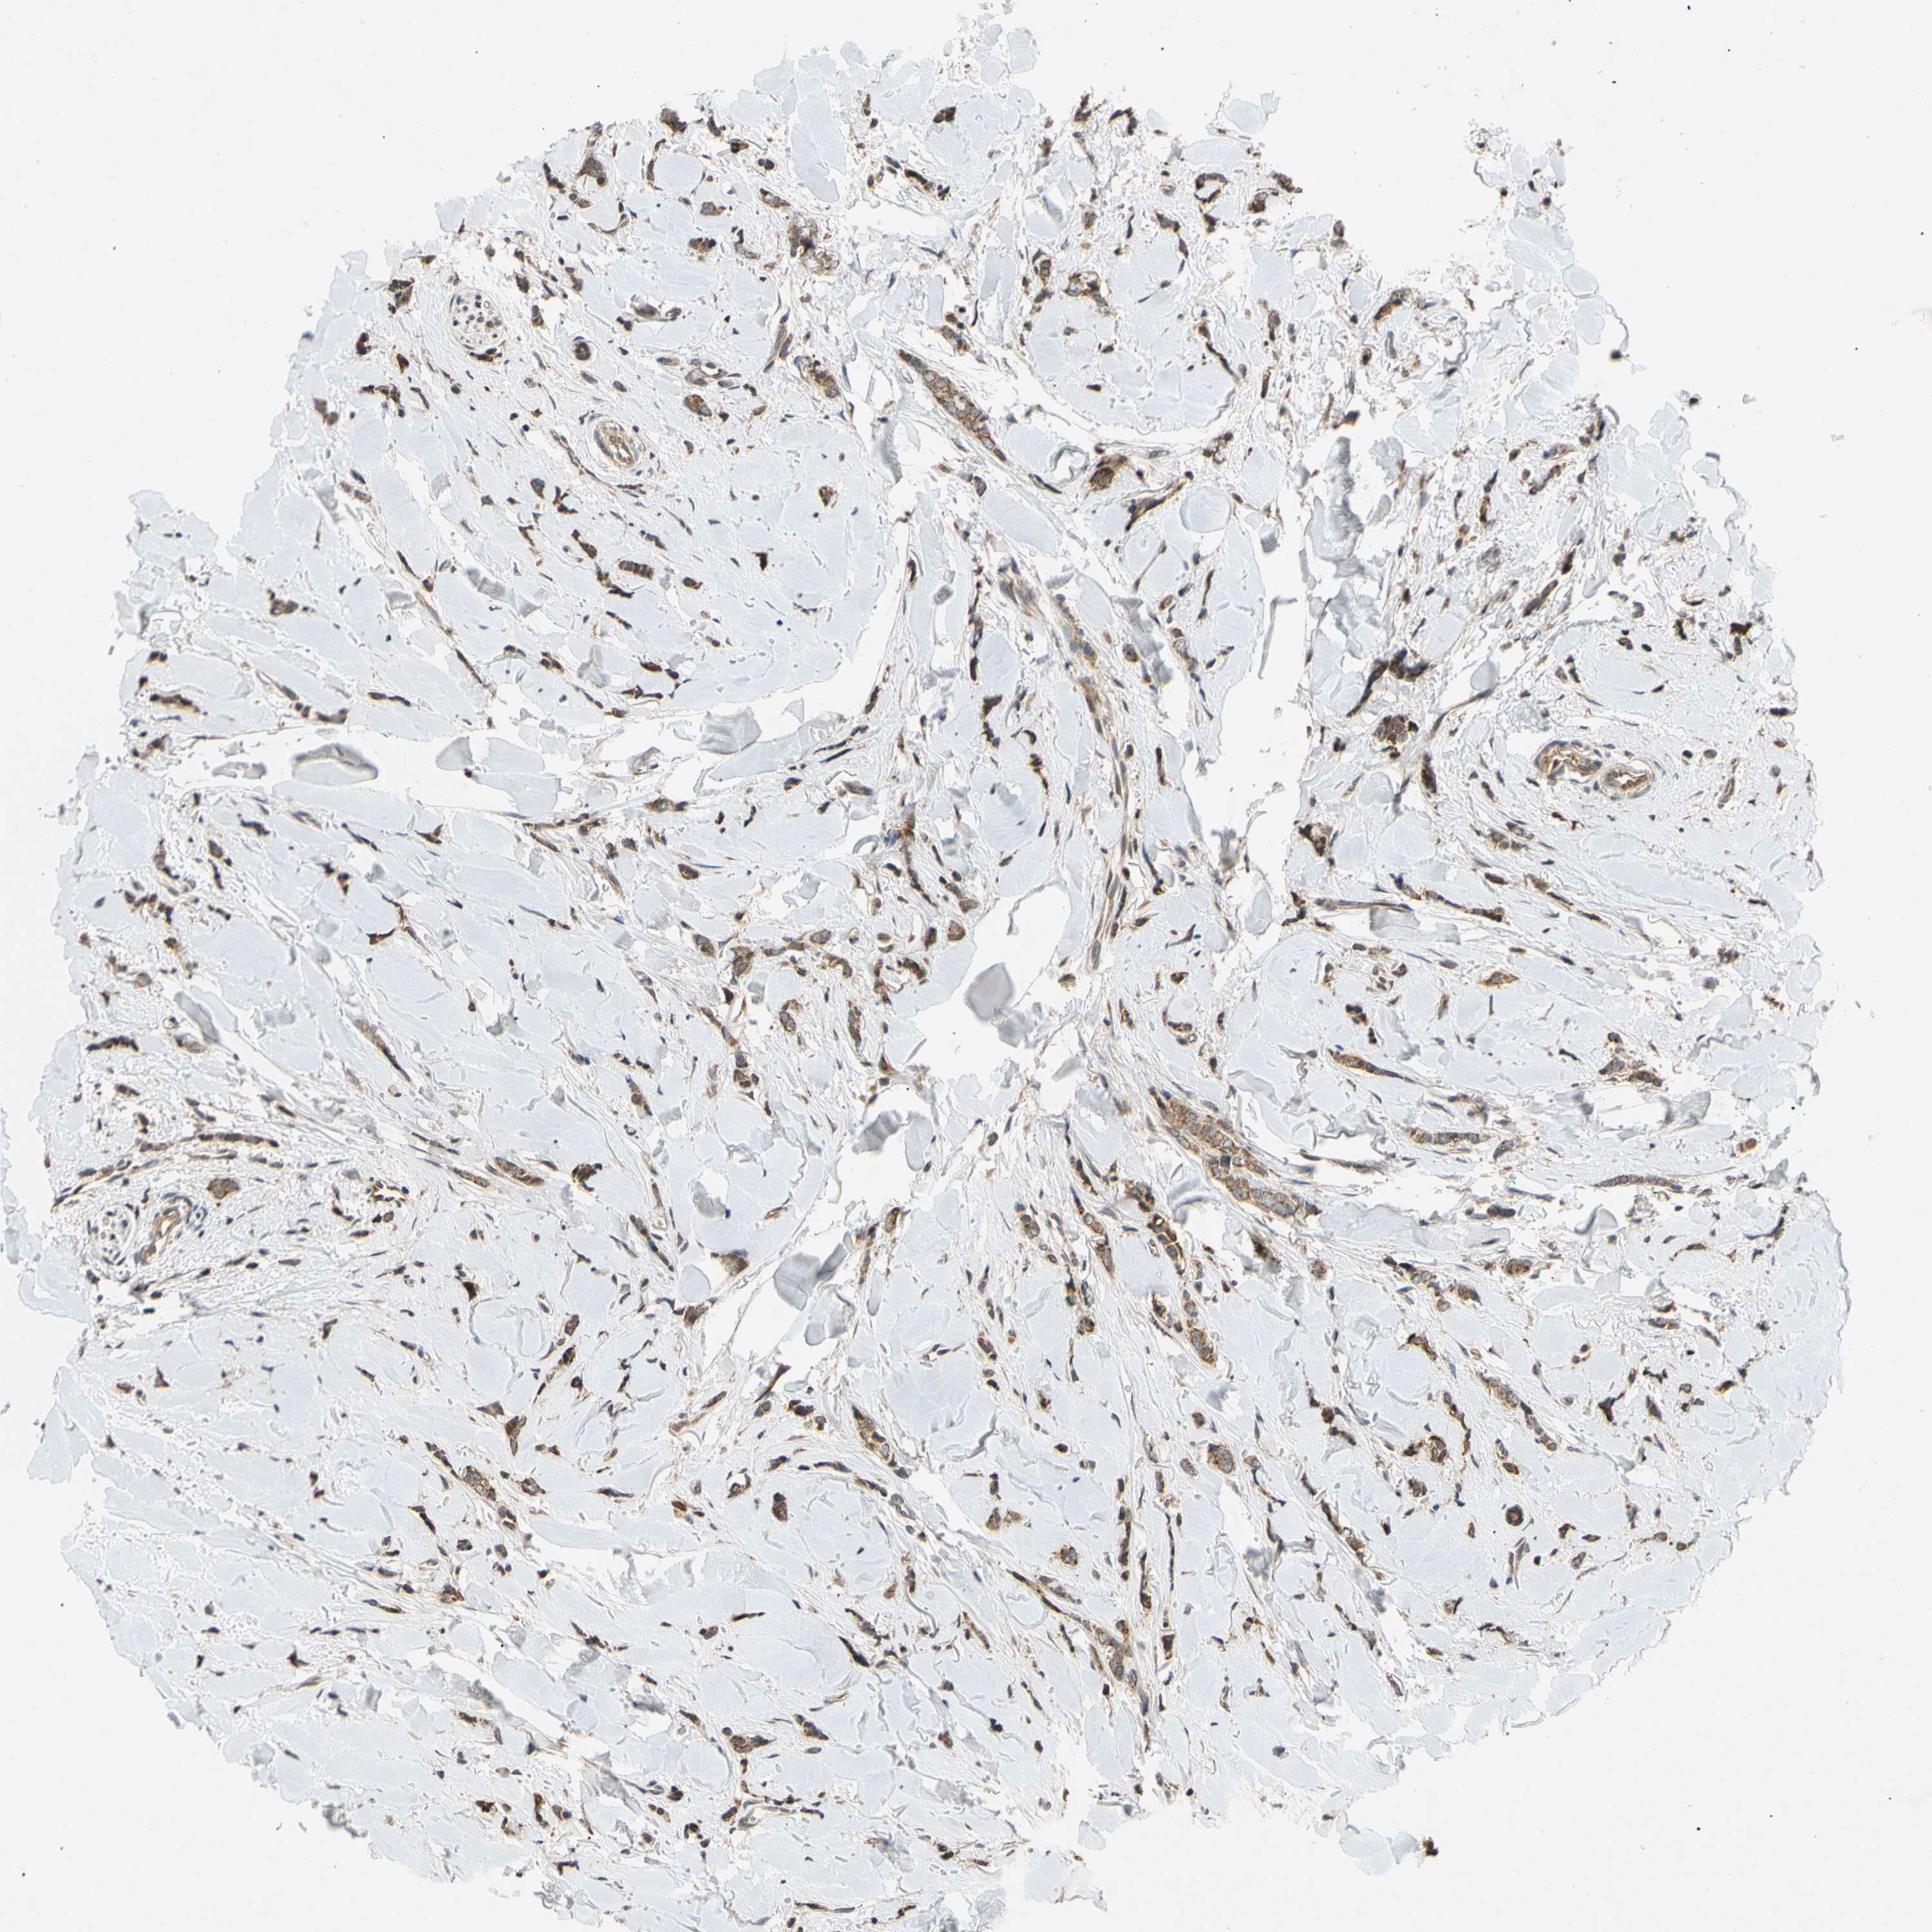

CANCER BREAST CANCER Show tissue menu

BRCA TCGA BRCA VALIDATION PROTEIN EXPRESSION